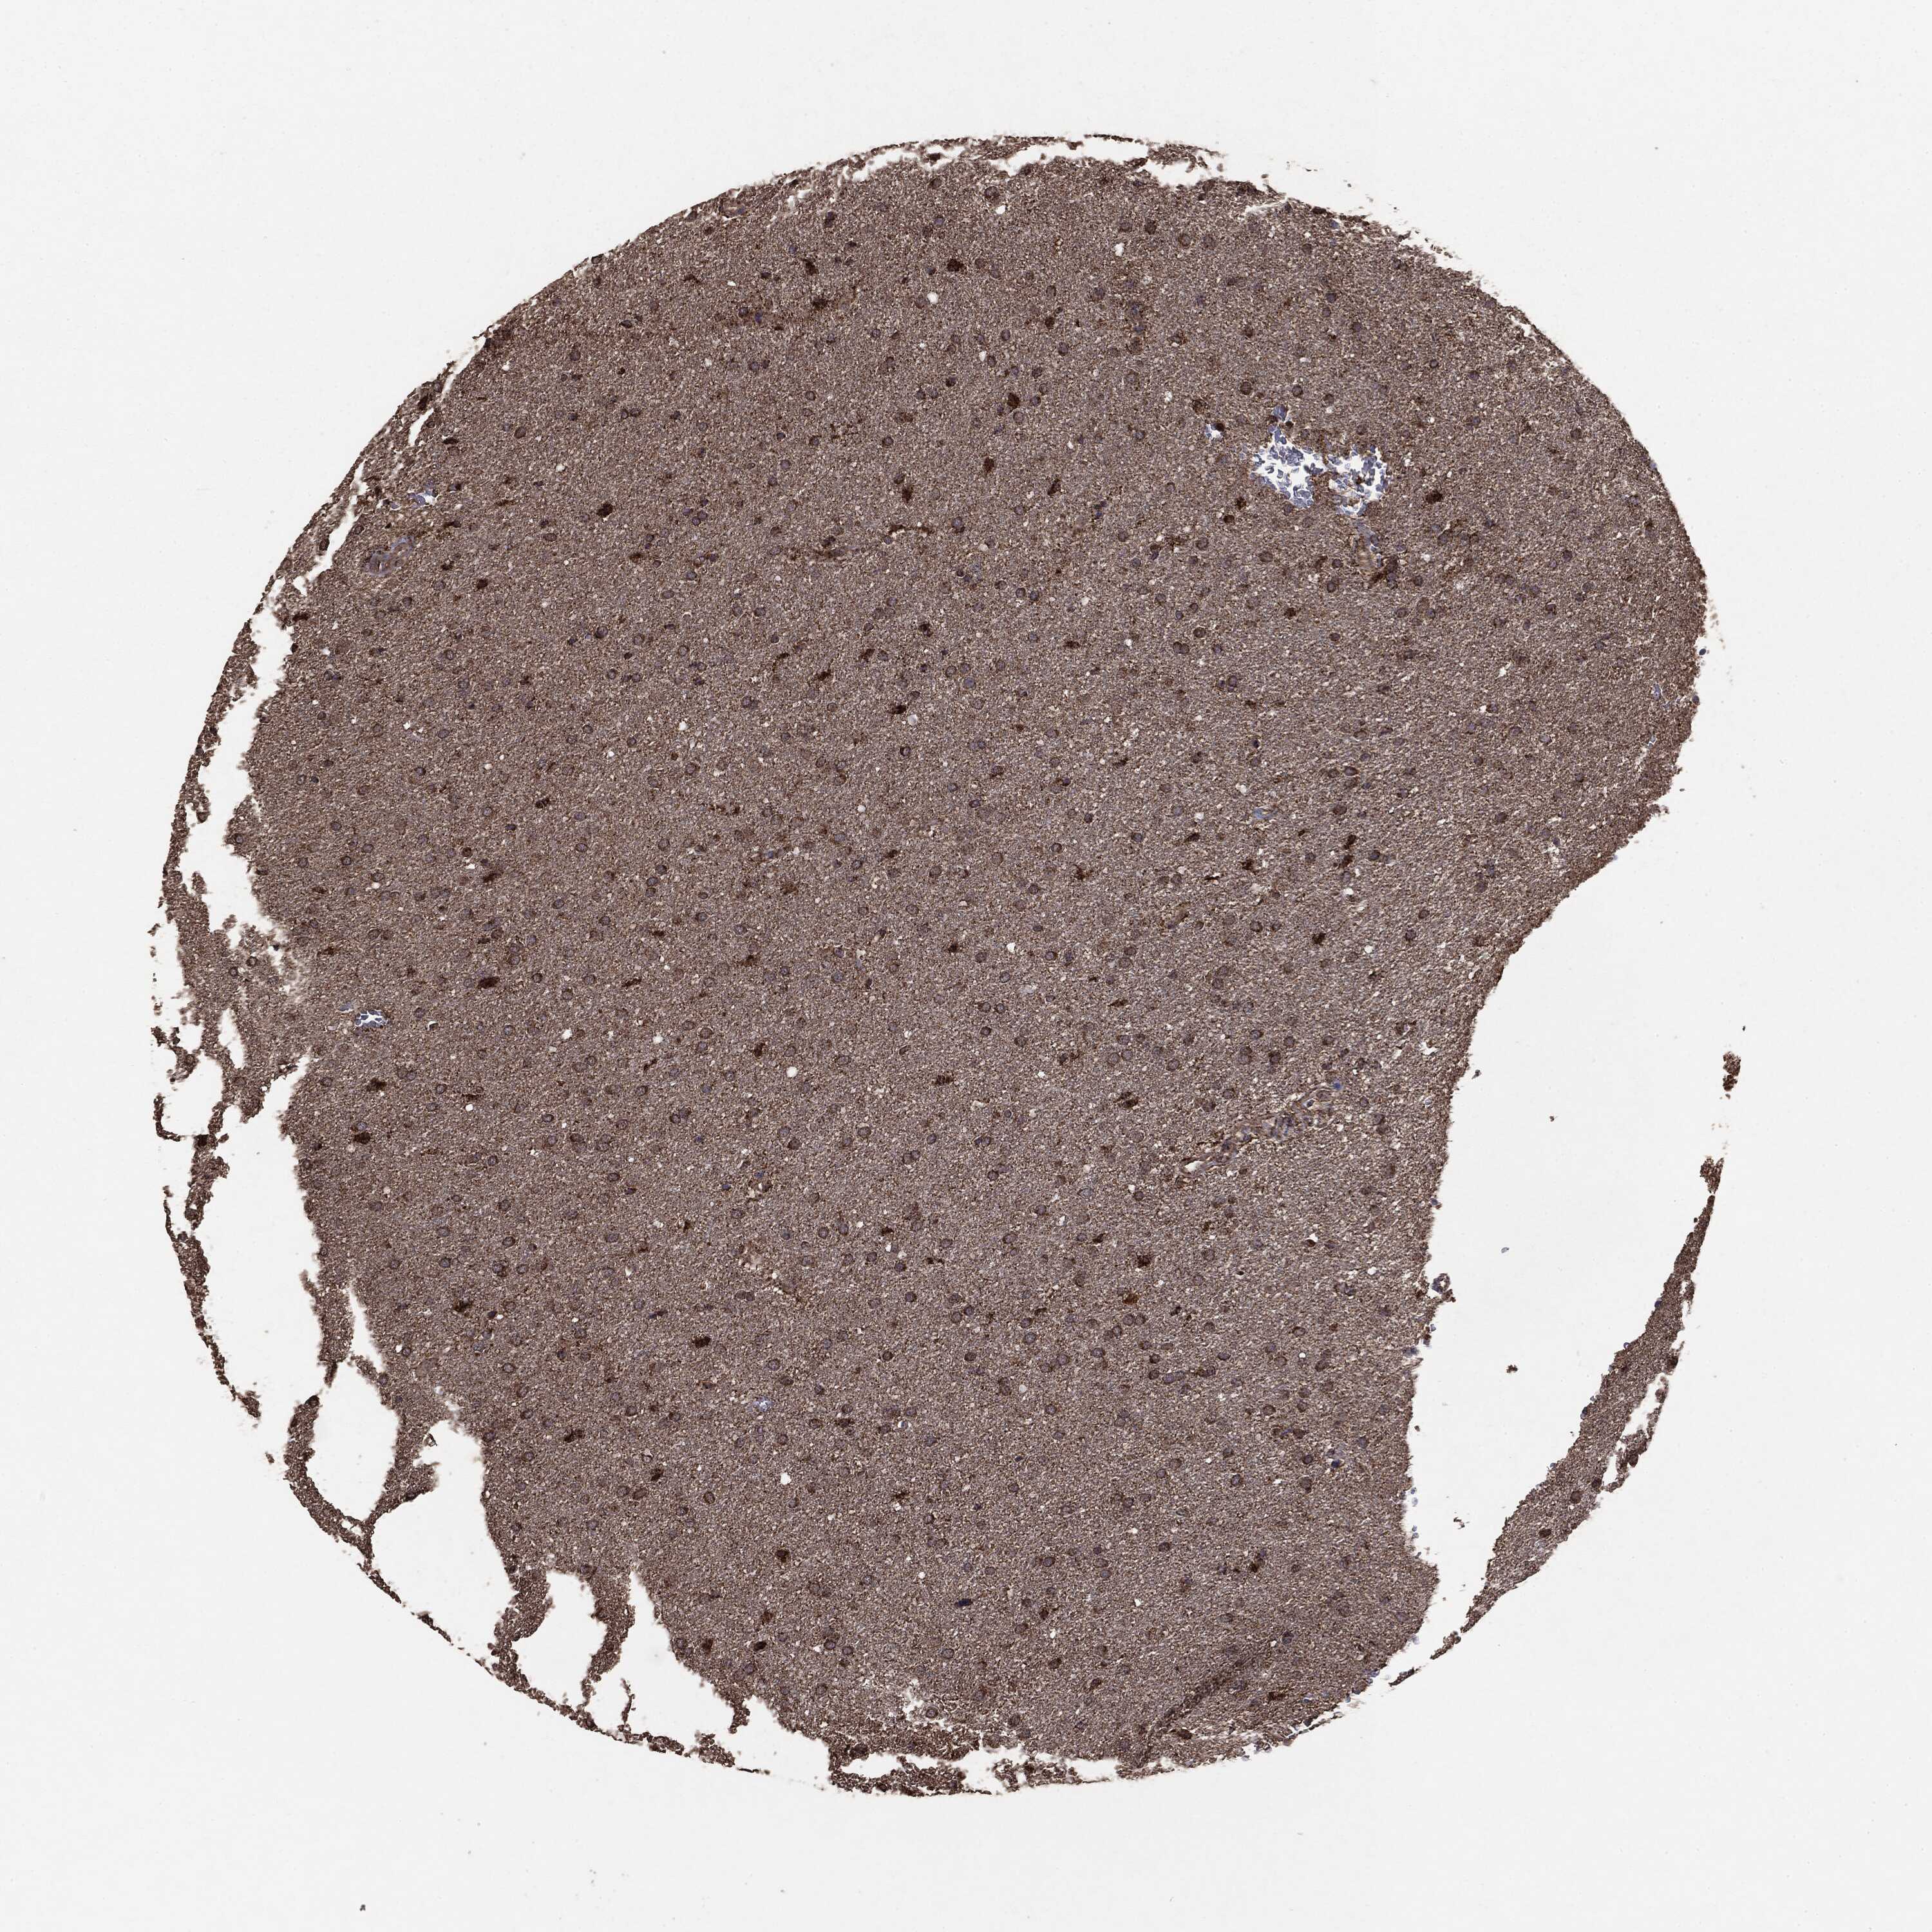

GLIOMA - Protein expressioni

A mouse-over function shows sample information and annotation data. Click on an image to view it in a full screen mode. Samples can be filtered based on level of antibody staining by selecting one or several of the following categories: high, medium, low and not detected. The assay and annotation is described here.

Note that samples used for immunohistochemistry by the Human Protein Atlas do not correspond to samples in the TCGA dataset.

Antibody stainingi

Antibody staining in the annotated cell types in the current human tissue is reported as not detected, low, medium, or high, based on conventional immunohistochemistry profiling in selected tissues. This score is based on the combination of the staining intensity and fraction of stained cells.

Each image is clickable and will lead to virtual microscopy that enables deeper exploration of all samples and also displays staining intensity scores, fraction scores and subcellular localization as well as patient and tissue information for each sample.

CAB069425

CAB080053

CAB080065

CAB080070

CAB080081

CAB080095

CAB080097

Staining

High

Medium

Low

Not detected

Intensity

Strong

Moderate

Weak

Negative

Quantity

>75%

75%-25%

<25%

None

Location

Nuclear

Cytoplasmic/membranous

Cytoplasmic/membranous,nuclear

Glioma, malignant, Low grade

Glioma, malignant, High grade

Glioma, malignant, NOS